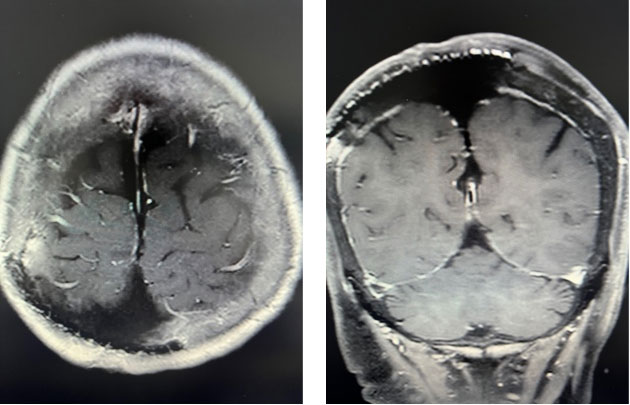

术后复查显示肿瘤切除很干净,术区没有渗血,没有积液,没有血肿,陈阿姨恢复很好,术后病理也提示为良性脑膜瘤,顺利出院。

甘武副主任医师、林晓风主任医师团队经过充分评估和术前准备,按计划进行手术,手术中将肿瘤连同受累及的颅骨、硬膜、静脉窦、大脑镰一并彻底切除,并完好保护正常脑组织和血管,修补硬膜,个体化定制修补颅骨,头皮塑形,一层层还原,手术非常顺利,出血很少。而且,手术按照陈阿姨的期待,没有剃光头,个体化设计最小切口,将手术的痕迹隐藏。